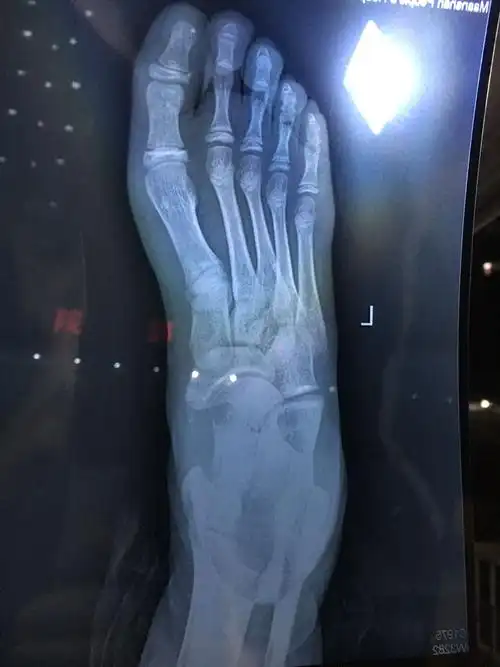

崴一脚骨折的可能性大么? - 知乎

医生说是撕脱性骨折,然后给我敷的膏药,现在就这样了.崴脚三天了

崴一脚骨折的可能性大么?

脚崴骨折了